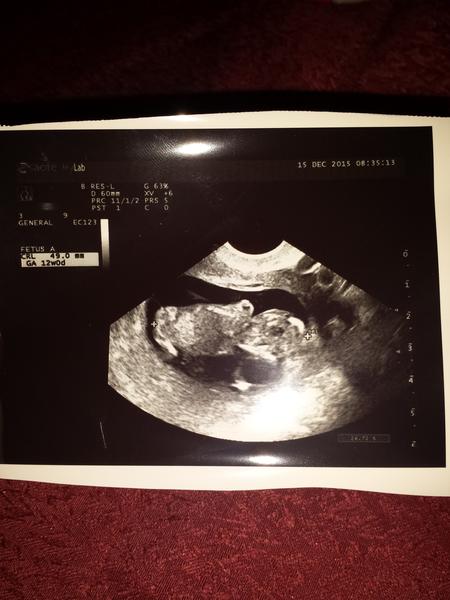

@sara34valentina @wewitta @mimikas @agathachristie @sara22 @melisssssa @evi789 ajojte dievcence moje tak ja uz mam to NT meranie za sebou, doktorka poriadne z kazdeho uhla popozerala drobceka, vyzera to tak ze je zatial vsetko v najlepsom poriadku, mame uz skoro 5cm a zistili sme ze drobec bude asi maly hamblosko po ocinkovi lebo ani za nic doktorke neukazal/a co medzi nozkami skryva 🙂 Dalsiu poradnu mame az 12.1. takze teraz mame pauzu od doktorov 🙂

@mimikas jeeej drobculiatko malinkeeee, presne tyzden je medzi nimi 😵 Mne dnes vyslo z utz ze som 12+0 🙂